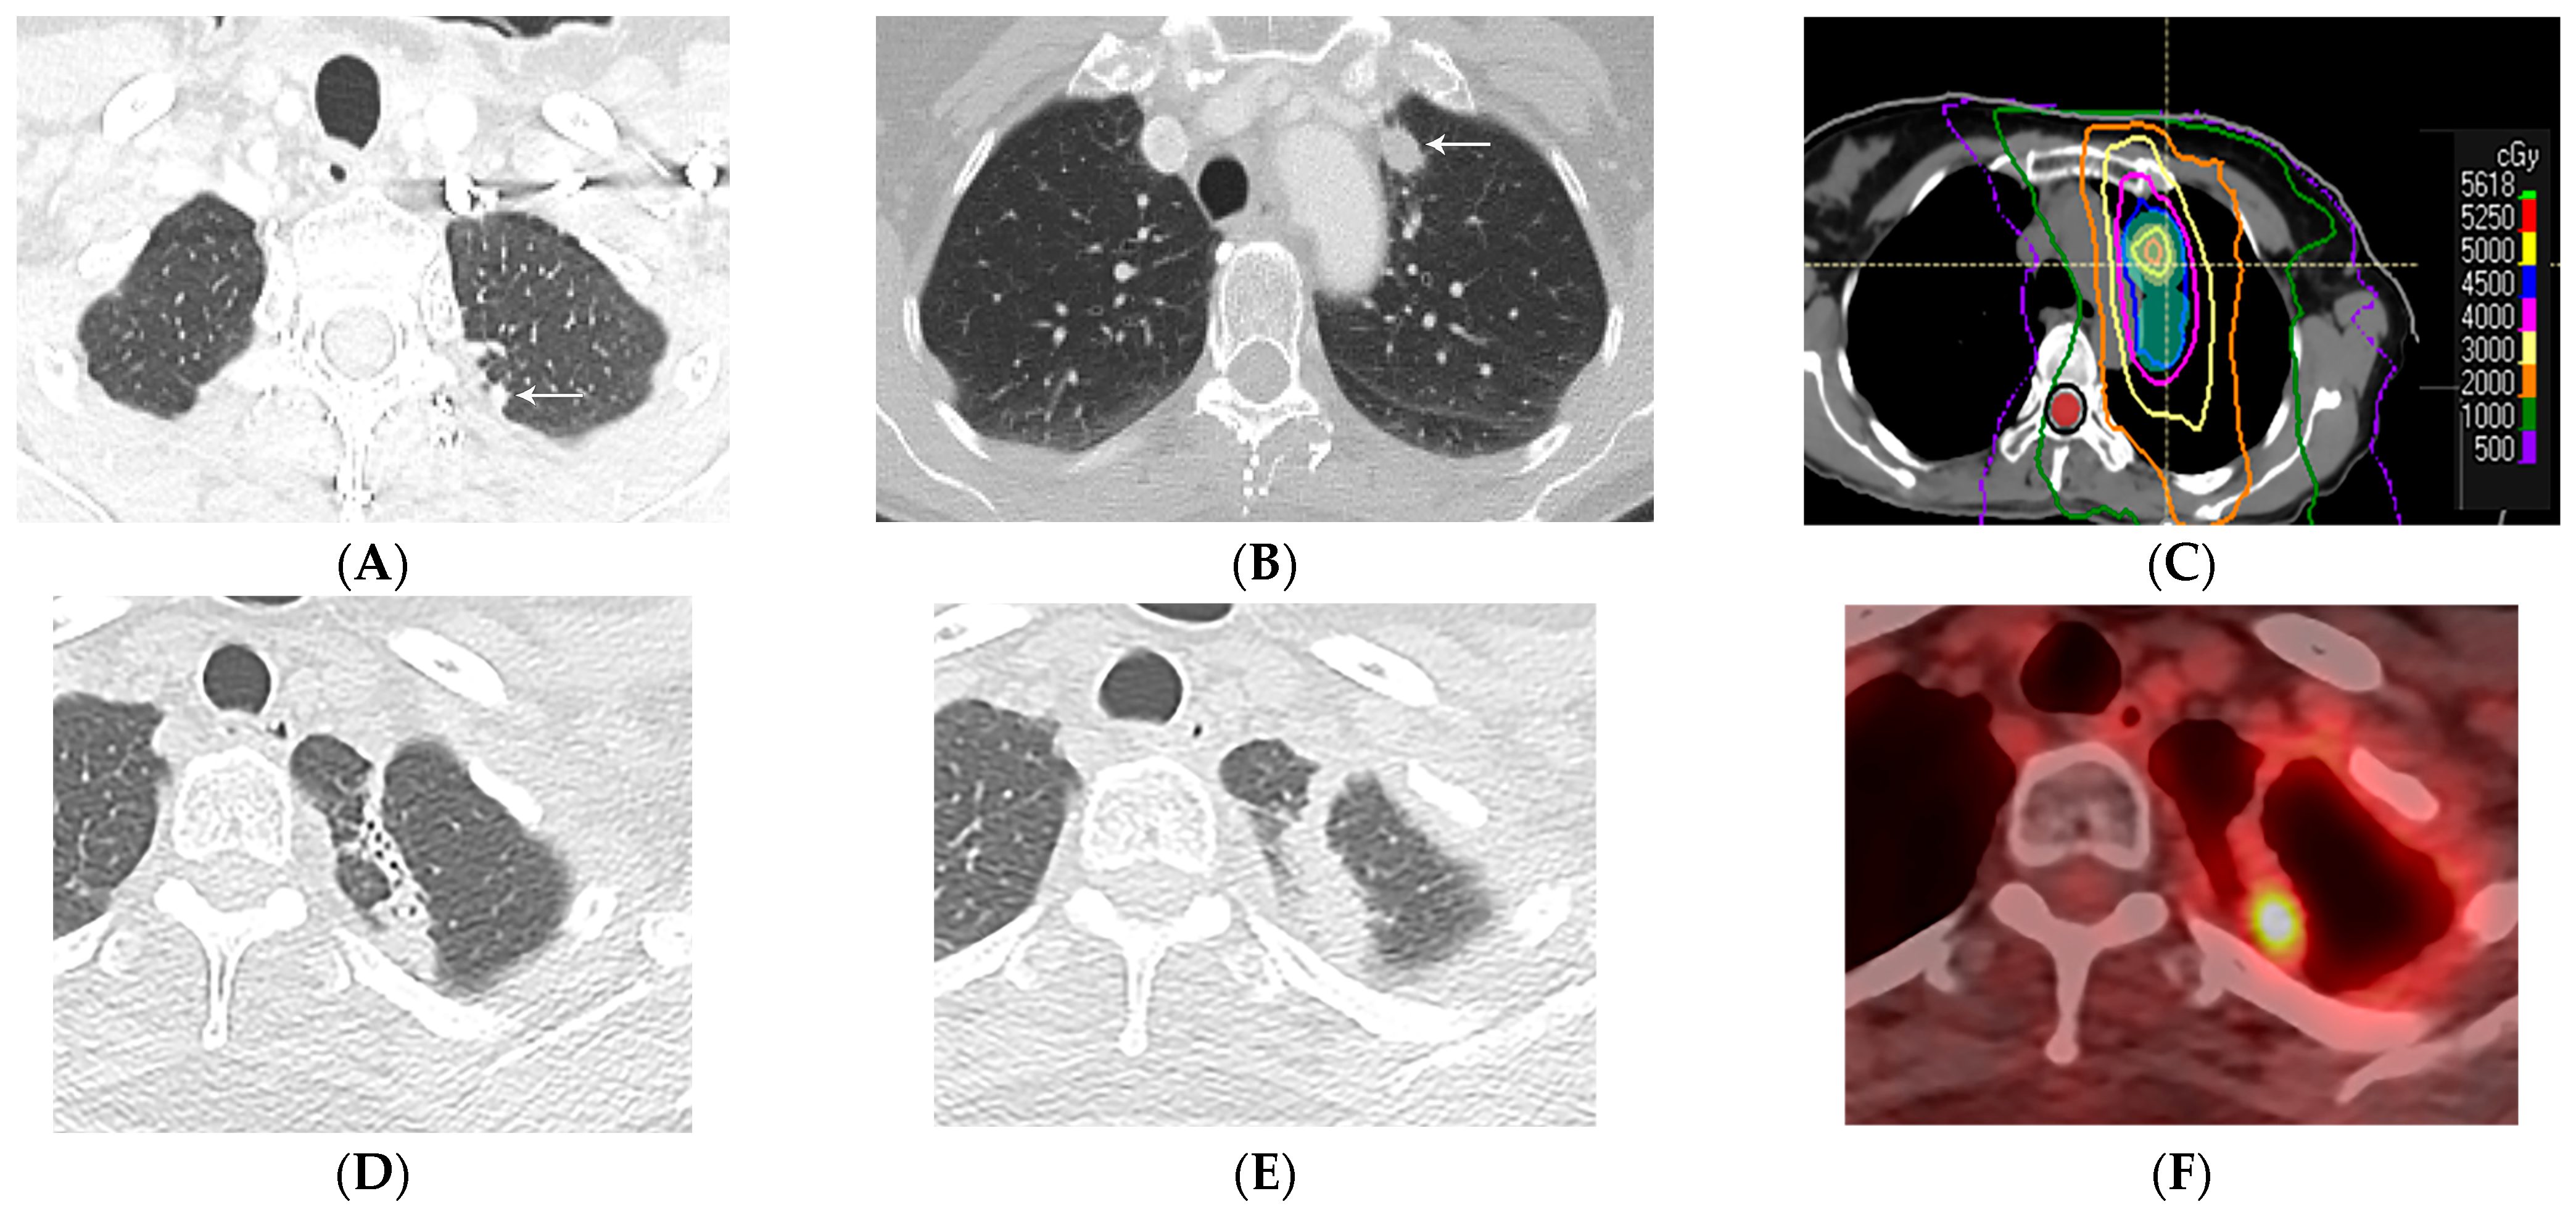

4.1. Modified Conventional Pattern

4.2. Mass-like Pattern

4.3. Scar-like Pattern

4.4. Organizing Pneumonia

5. Imaging Modalities and Radiomics